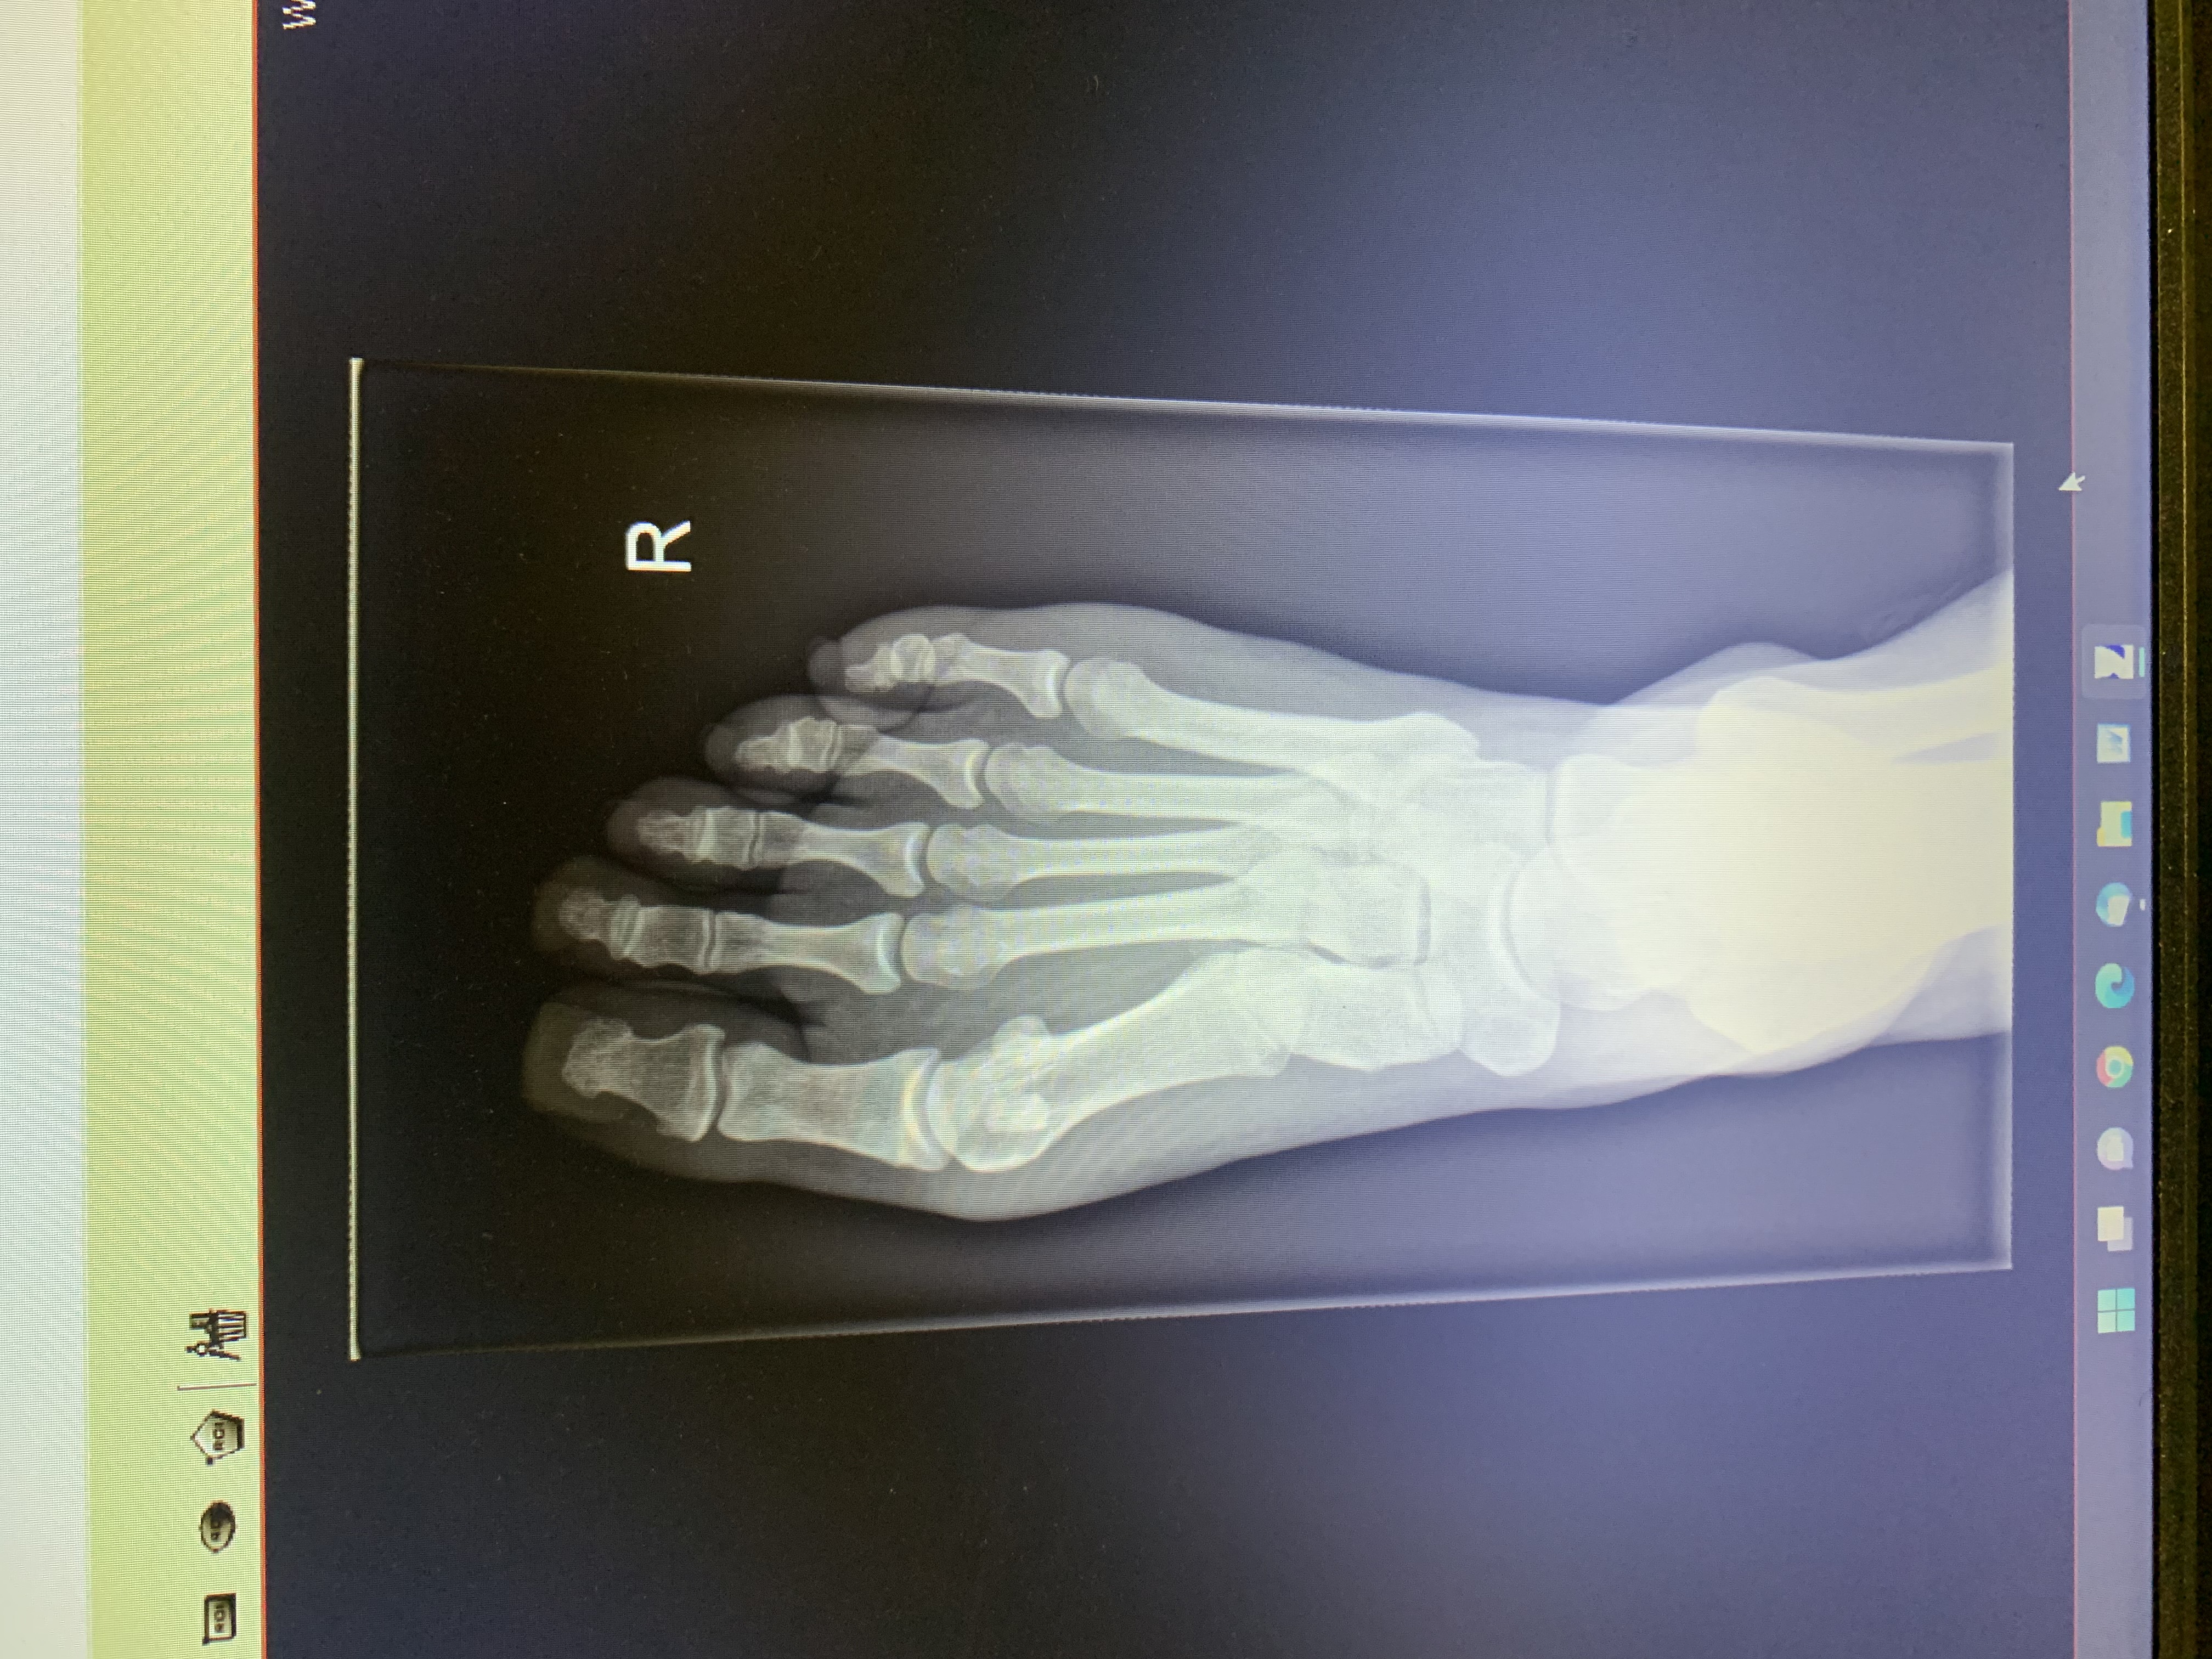

Witam, po weselu mam okropną opuchliznę w okolicy haluksa i dużego palca, ból ma charakter narywającego, w załączeniu zdjęcie. Co to może być?

Zapalenie wysiękowe kaletki od przeciążeń. Powinno samo przejść, można stosować plastry, żele i na okres przejściowy luźniejsze obuwie.Masaż żelami np;Biszolin, żel, balsam mineralny z biszofitem